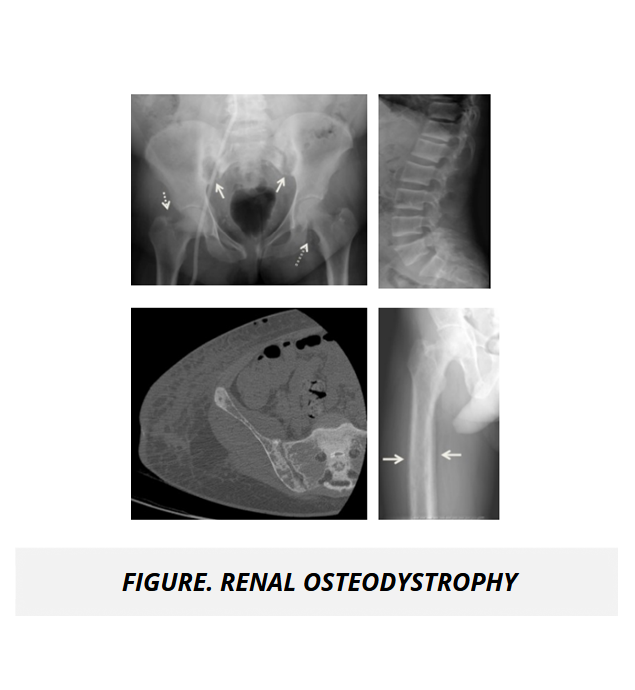

The UMock USMLE® Step 1 prep course features high quality pathologic images, gross and microscopic views, as well as radiologic imaging illustrating key concepts, disorders, and abnormal processes to help you gain a complete understanding of subject material.

The course features detailed tables and high quality radiologic and gross images to help you conceptualize the application of medicine for normal and abnormal body system processes and pathologies in rheumatology and the musculoskeletal system.